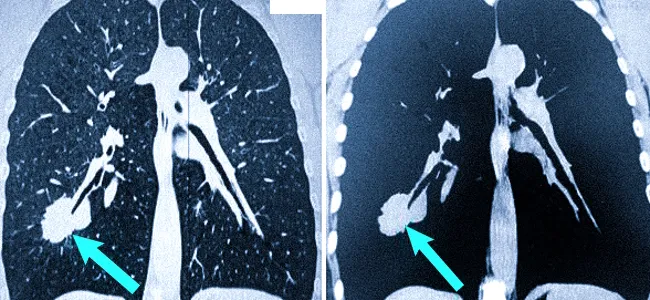

Спікулоподібні / шипоподбіні контури («промені»)

Утворення чи вузлики в легенях можуть мати гладку поверхню або нерівну поверхню через наявність шипів (виступів або гострих кінчиків) або лобулів (вигляд декількох округлих вузликів разом).

Однією з характерних ознак злоякісного процесу є спікулоподібні (шипоподбіні) контури. Це означає, що краї утворення виглядають нерівними і мають вигляд «променів», які розходяться в навколишню тканину. Такі контури можуть свідчити про інвазивний ріст пухлини та її проростання в навколишні тканини.

На відміну від доброякісних утворень, які часто мають чіткі й рівні межі, злоякісні зміни частіше виглядають «рваними» та неоднорідними.